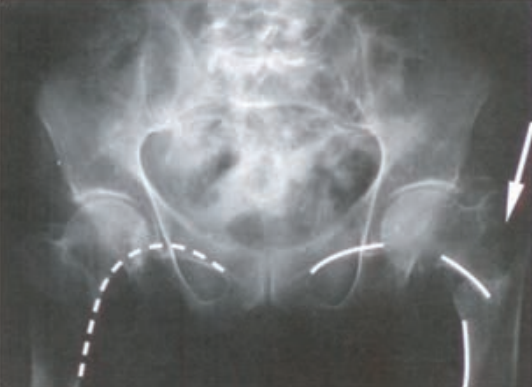

Które badanie zostało zarejestrowane na przedstawionym radiogramie?

Ilustracja do pytania 31

A. Dróg żółciowych metodą cholangiografii śródoperacyjnej.

B. Płuc wykonane metodą Przybylskiego.

C. Jamy brzusznej wykonane poziomą wiązką promieniowania.

D. Układu moczowego z użyciem środka kontrastującego.